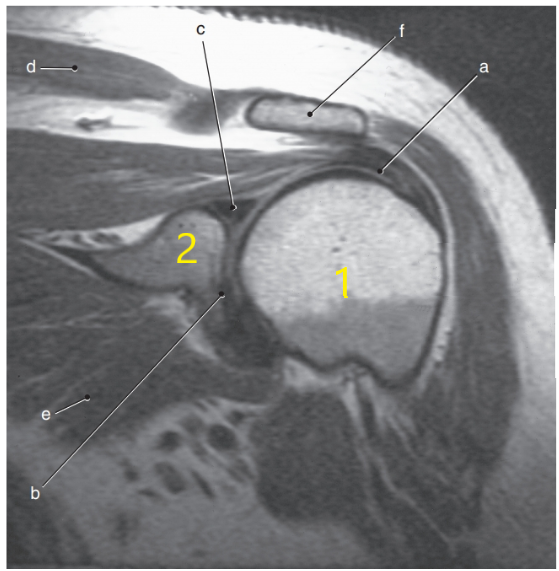

What anatomy is # 1 ?

Humeral head

What anatomy is # 2 ?

Scapula

What is letter c ?

Superior glenoid labrum

What is letter C pointing to ?

Coracoid process

What is letter f ?

Acromion process

What is letter b ?

Supraspinatus muscle

What is letter d ?

Acromioclavicular ligament

Subscapularis tendon